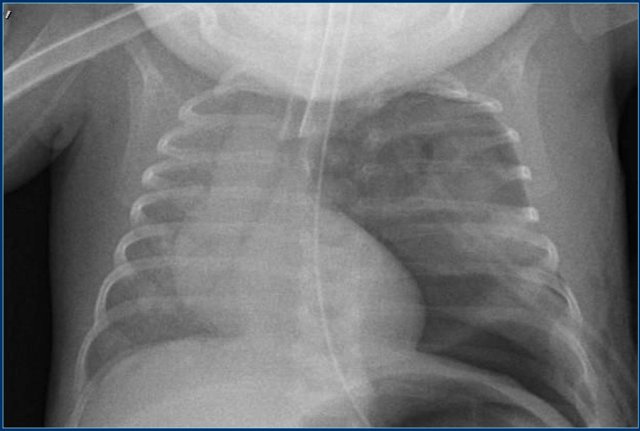

Endotracheal tube

The tip of an endotracheal tube should be inbetween the thoracic aperture and 1 cm above the carina.

The tip travels downward if the neck is flexed or upward if the neck is extended.

The most common malpositioning is in the right mainstem bronchus, because of the shallower angle of the right main bronchus.

Here a good positioned tube in a patient with a pneumothorax on the left.